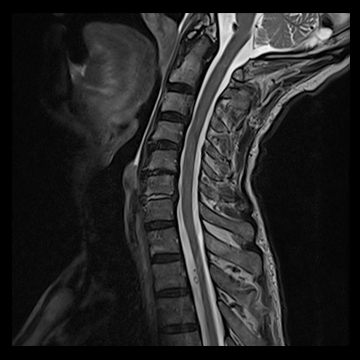

頚椎

T1 TSE, 384 matrix,

T2 TSE, 384 matrix,

T1 TIRM, 320 matrix,

全脊椎

T1 TSE, 448 matrix

T2 STIR, 384 matrix,